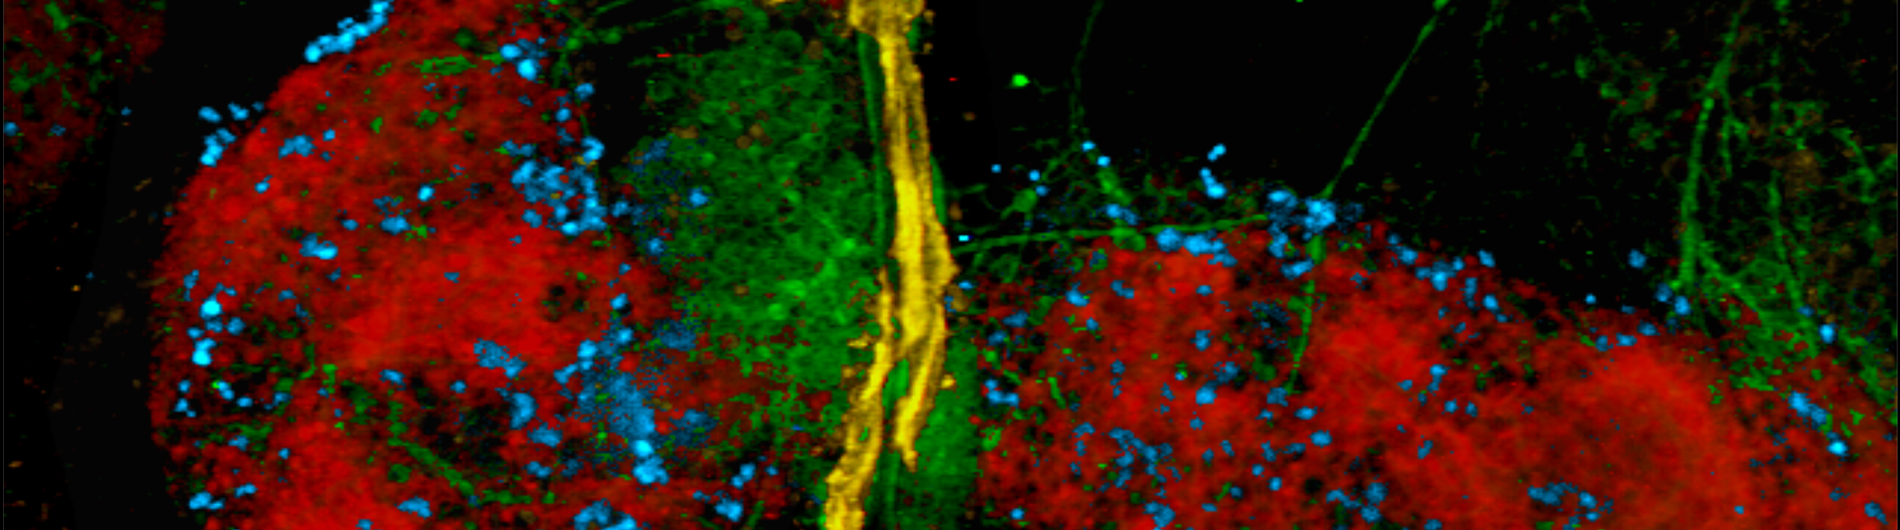

Immune cells (orange) and blood vessels (green) inside of the tumor

A major obstacle blocking the way for effective cancer therapy is the tumor microenvironment. Within the tumor consists a multitude of various components ranging from cancer cells, fibroblasts, blood vessels, immune cells, nerves, bacteria, etc. Cancerous cells “program” the components of the tumor microenvironment to promote the growth of the malignancy through the production and interaction of a very complex milieu of cancer-driving factors. The Gerber lab focuses on understanding the complexities of the tumor microenvironment to identify what factors promote tumor growth and, from this data, develop therapies to counteract these molecules.

Crosstalk between the Nervous and Immune Systems within the Tumor